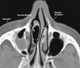

Concha bullosa

A concha bullosa is a pneumatized (air-filled) cavity within a nasal concha, also known as a turbinate. Bullosa refers to the air-filled cavity within the turbinate. [Source: Wikipedia ]